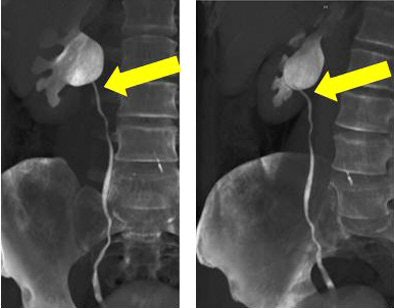

![]() |

| Volume-rendered CT images obtained during 64-channel CTU with interactive display of the collecting system and the relation of the right renal pelvis to the proximal ureter with interactive manipulation of the isotropic dataset. Images courtesy of Dr. Terri Vrtiska, Mayo Clinic, Rochester, MN. |